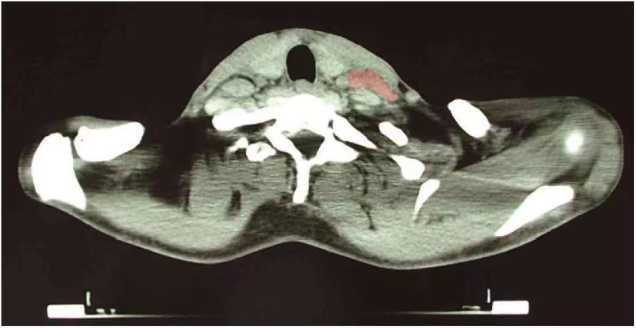

一位霍奇金淋巴瘤的颈部CT提示左侧颈部淋巴结肿大(红色阴影部分)